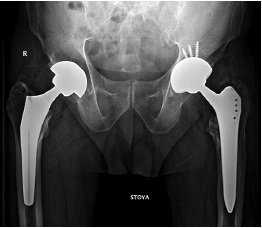

Sequential X-ray methods of research using plain pelvic radiography in the antero-posterior view revealed a satisfactory inclination of the acetabular component, a varus position of the femoral component of 10°, and a distortion of the endoprosthesis contours in the lower region of the acetabular component and the femoral neck component, which was regarded as a fracture of the ceramic liner or head that make up the bearings. Signs of a previously installed DHS surgical hardware, as well as channels from previously inserted cortical and dynamic screws, were visualized in the cortical area in the upper third of the diaphysis of the left femoral bone after removal in the diaphyseal and subtrochanteric regions (Fig. 1, 2).

Fig. 1. Overview X-ray of the hip joints: on the right — a total hip replacement with a cementless proximal fixation (2019); jn the left — a total hip replacement with a cementless proximal fixation. Dislocation of the elements of the bearing (highlighted in red). The arrows indicate the canals after removal of the screws